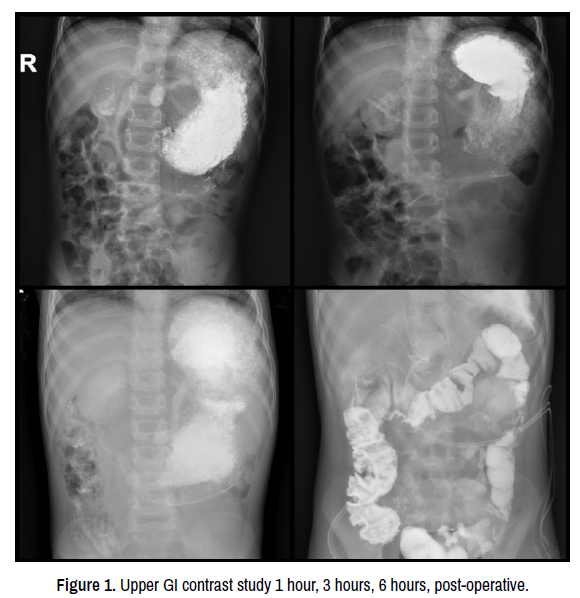

Histopathological examination of the accessory hepatic lobe showed fibrosis in the resected mass, with mild portal inflammation and moderate hepatitis. Postoperative MRI showed a 6 mm left hepatic duct that drains the left liver lobe, the caudate lobe and the 6th and 7th liver segments with a stent in place at this level, a 7 mm hepatic duct that drains the 8th segment with a stent in place and a 6 mm hepatic duct that drains the 5th segment. The last two ducts seem to converge into a common duct. The common bile duct has a filiform morphology and can be seen opening into the duodenum separately from the pancreatic duct, but the proximal segment can be observed just cranially to the pancreas and has a 3 mm dilatation (Figure 4). Seven days after the first surgery a median laparotomy was performed. Almost 100 ml of bile were evacuated, and the previously stented hepatic ducts were identified. The ducts were dissected and a common hepatic duct was identified that had been previously ligated. A hepatic oduodenstomy was performed, after mobilisation of the 2nd segment of the duodenum. The bowel loops were positioned in nonrotation, with the small bowel loops situated in the right hemi abdomen and the colon in the left hemi abdomen. The patient’s postoperative course was favourable, with enteral feeding resuming in postoperative day 4. Ultrasound evaluation showed an 88.5 mm right liver lobe and a 39 mm left liver lobe, with normal structure, a 9 mm portal vein, with minimal dilatation of the intrahepatic ducts of 1.7 mm. Laboratory examination showed decreasing liver enzymes levels. The patient was discharged on postoperative day 9.

clinical-case-reports-post-operative-mrcp

Figure 4. Post-operative MRCP.